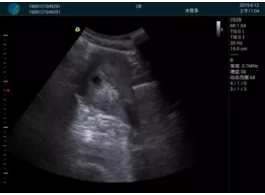

清晰顯示孕囊,通過軟件包計算孕齡7w+6d

M20實時引導(dǎo),術(shù)中清晰顯示孕囊被破壞和抽吸針的過程,清晰顯示吸引針

抽吸結(jié)束后縱切子宮,孕囊已被完全抽吸,未見明顯殘留